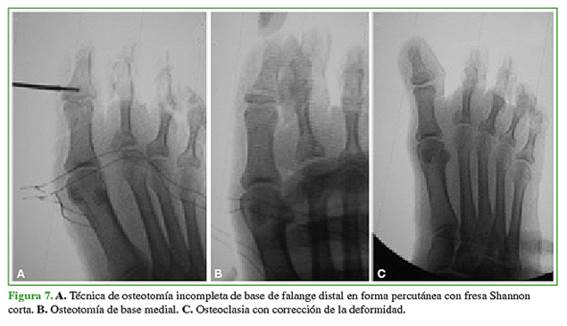

Se describen los pasos principales: se coloca al paciente en decúbito dorsal con anestesia troncular en el hallux por operar. Se realiza un portal medial en la base de la falange distal 5 mm distal a la articulación, con bisturí Beaver 64, bajo control fluoroscópico, hasta llegar al hueso. Tener como referencia el comienzo de la matriz ungueal y proceder con cuidado para no lesionarla, ya que está inmediatamente distal al sitio de la osteotomía.

Luego, con una fresa Shannon corta a bajas revoluciones, se realiza una osteotomía incompleta de base medial paralela a la superficie articular para no lesionar la matriz que, según el ángulo de deformidad por corregir, su base será mayor o menor. Se controla con fluoroscopia. Se mantiene intacta la pared lateral de la falange distal y su periostio. Esto permite que la osteotomía sea autoestable (Figura 7).

Por último, se procede con la osteoclasia y la corrección de la deformidad. Control con fluoroscopia. Cierre con un punto de nailon 4.0 (Figura 8). Vendaje corrector durante tres semanas, manteniendo el objetivo logrado, para conseguir la consolidación en la posición deseada. Calzado de posoperatorio con apoyo inmediato. Al mes de la cirugía, se permite el uso progresivo del calzado normal, según la tolerancia.

Nota: En caso de inestabilidad de la osteotomía por sección completa ósea, se puede estabilizar transitoriamente con una aguja de Kirschner por tres semanas para evitar desviaciones inadecuadas. Esto es poco probable con la cirugía mínimamente invasiva.